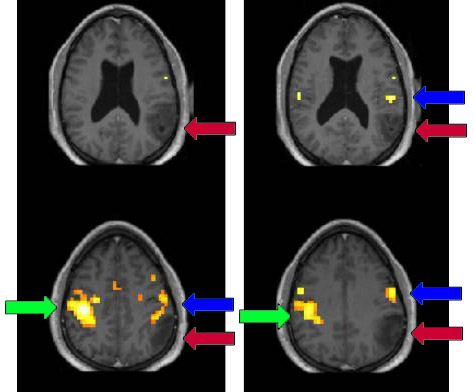

Example of a language task with fMRI showing activation (yellow arrows) far removed from an enhancing tumor (blue arrows):

Example of a patient with a left parietal tumor (red arrows) performing a left hand motor task; primary right motor cortical activation (green arrows) is seen, but displacement of left hemispheric activation (blue arrows) is also demonstrated. Some of the left hemispheric activation borders on the margins of the tumor. Knowing this will help a neurosurgeon decide how much of a tumor can be safely removed without causing a postoperative permanent neurological deficit (e.g., paralysis, numbness, or difficulty with movement).